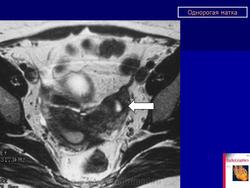

МПС. Женская репродуктивная система. Аномалии и варианты развития. Матка. Однорогая матка. +

Аномалии и варианты развития. Однорогая матка.